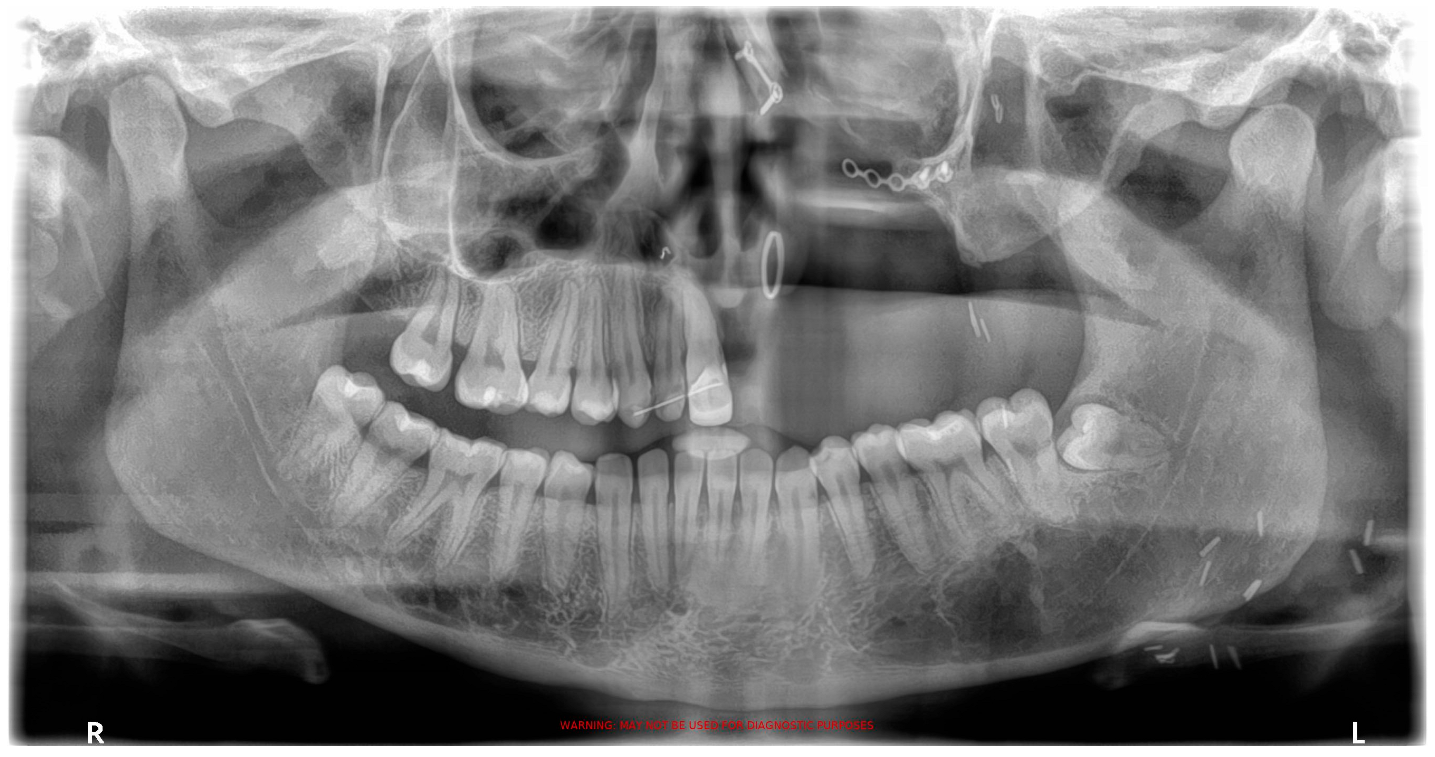

The fibroma was surgically excised. A bone graft harvested from the right scapula was placed in the defective area; however, due to the lack of vascularization, the graft was rejected. A second graft, taken from the left scapula, was also unsuccessful. Later on, a custom removable appliance was manufactured to restore function, esthetics, and facial contour of the stomatognathic system. The prosthesis on the dental cast is shown in Figure 1a, while Figure 1b shows the frontal view of the same cast. The occlusal anatomy of the edentulous defect is visualized in Figure 2a. The upper right central incisor was intruded, and a tooth extension of the removable appliance in #11 space was added. The appliance extended into the defective area, and an important feature was the hollow design of the segment extending into the sinus cavity, which contributed to increased retention while minimizing weight (Figure 2b). Over the course of time, the appliance had been periodically modified as needed to accommodate craniofacial growth and the development of neighboring structures. By October 2023, the patient had undergone orthodontic tooth movement with fixed appliances for space closure of the upper right quadrant. A panoramic radiograph was obtained, demonstrating the left-sided maxillary resection and completed orthodontic space closure, with preserved dental alignment on the contralateral side (Figure 3).

Figure 3. Panoramic radiograph after orthodontic treatment.